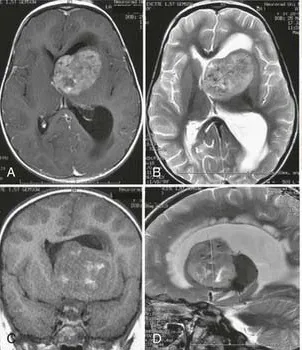

▼脑瘤凶猛侵袭▼ 短短4年,遭遇4次复发,每次复发都伴随着肿瘤的一再恶化。Ki-67指数更是从1%飙升至30%!7岁孩童究竟遭遇了什么骇人脑瘤,他又是如何逃出生天的? 额骨肿块揪出脑瘤谜团...